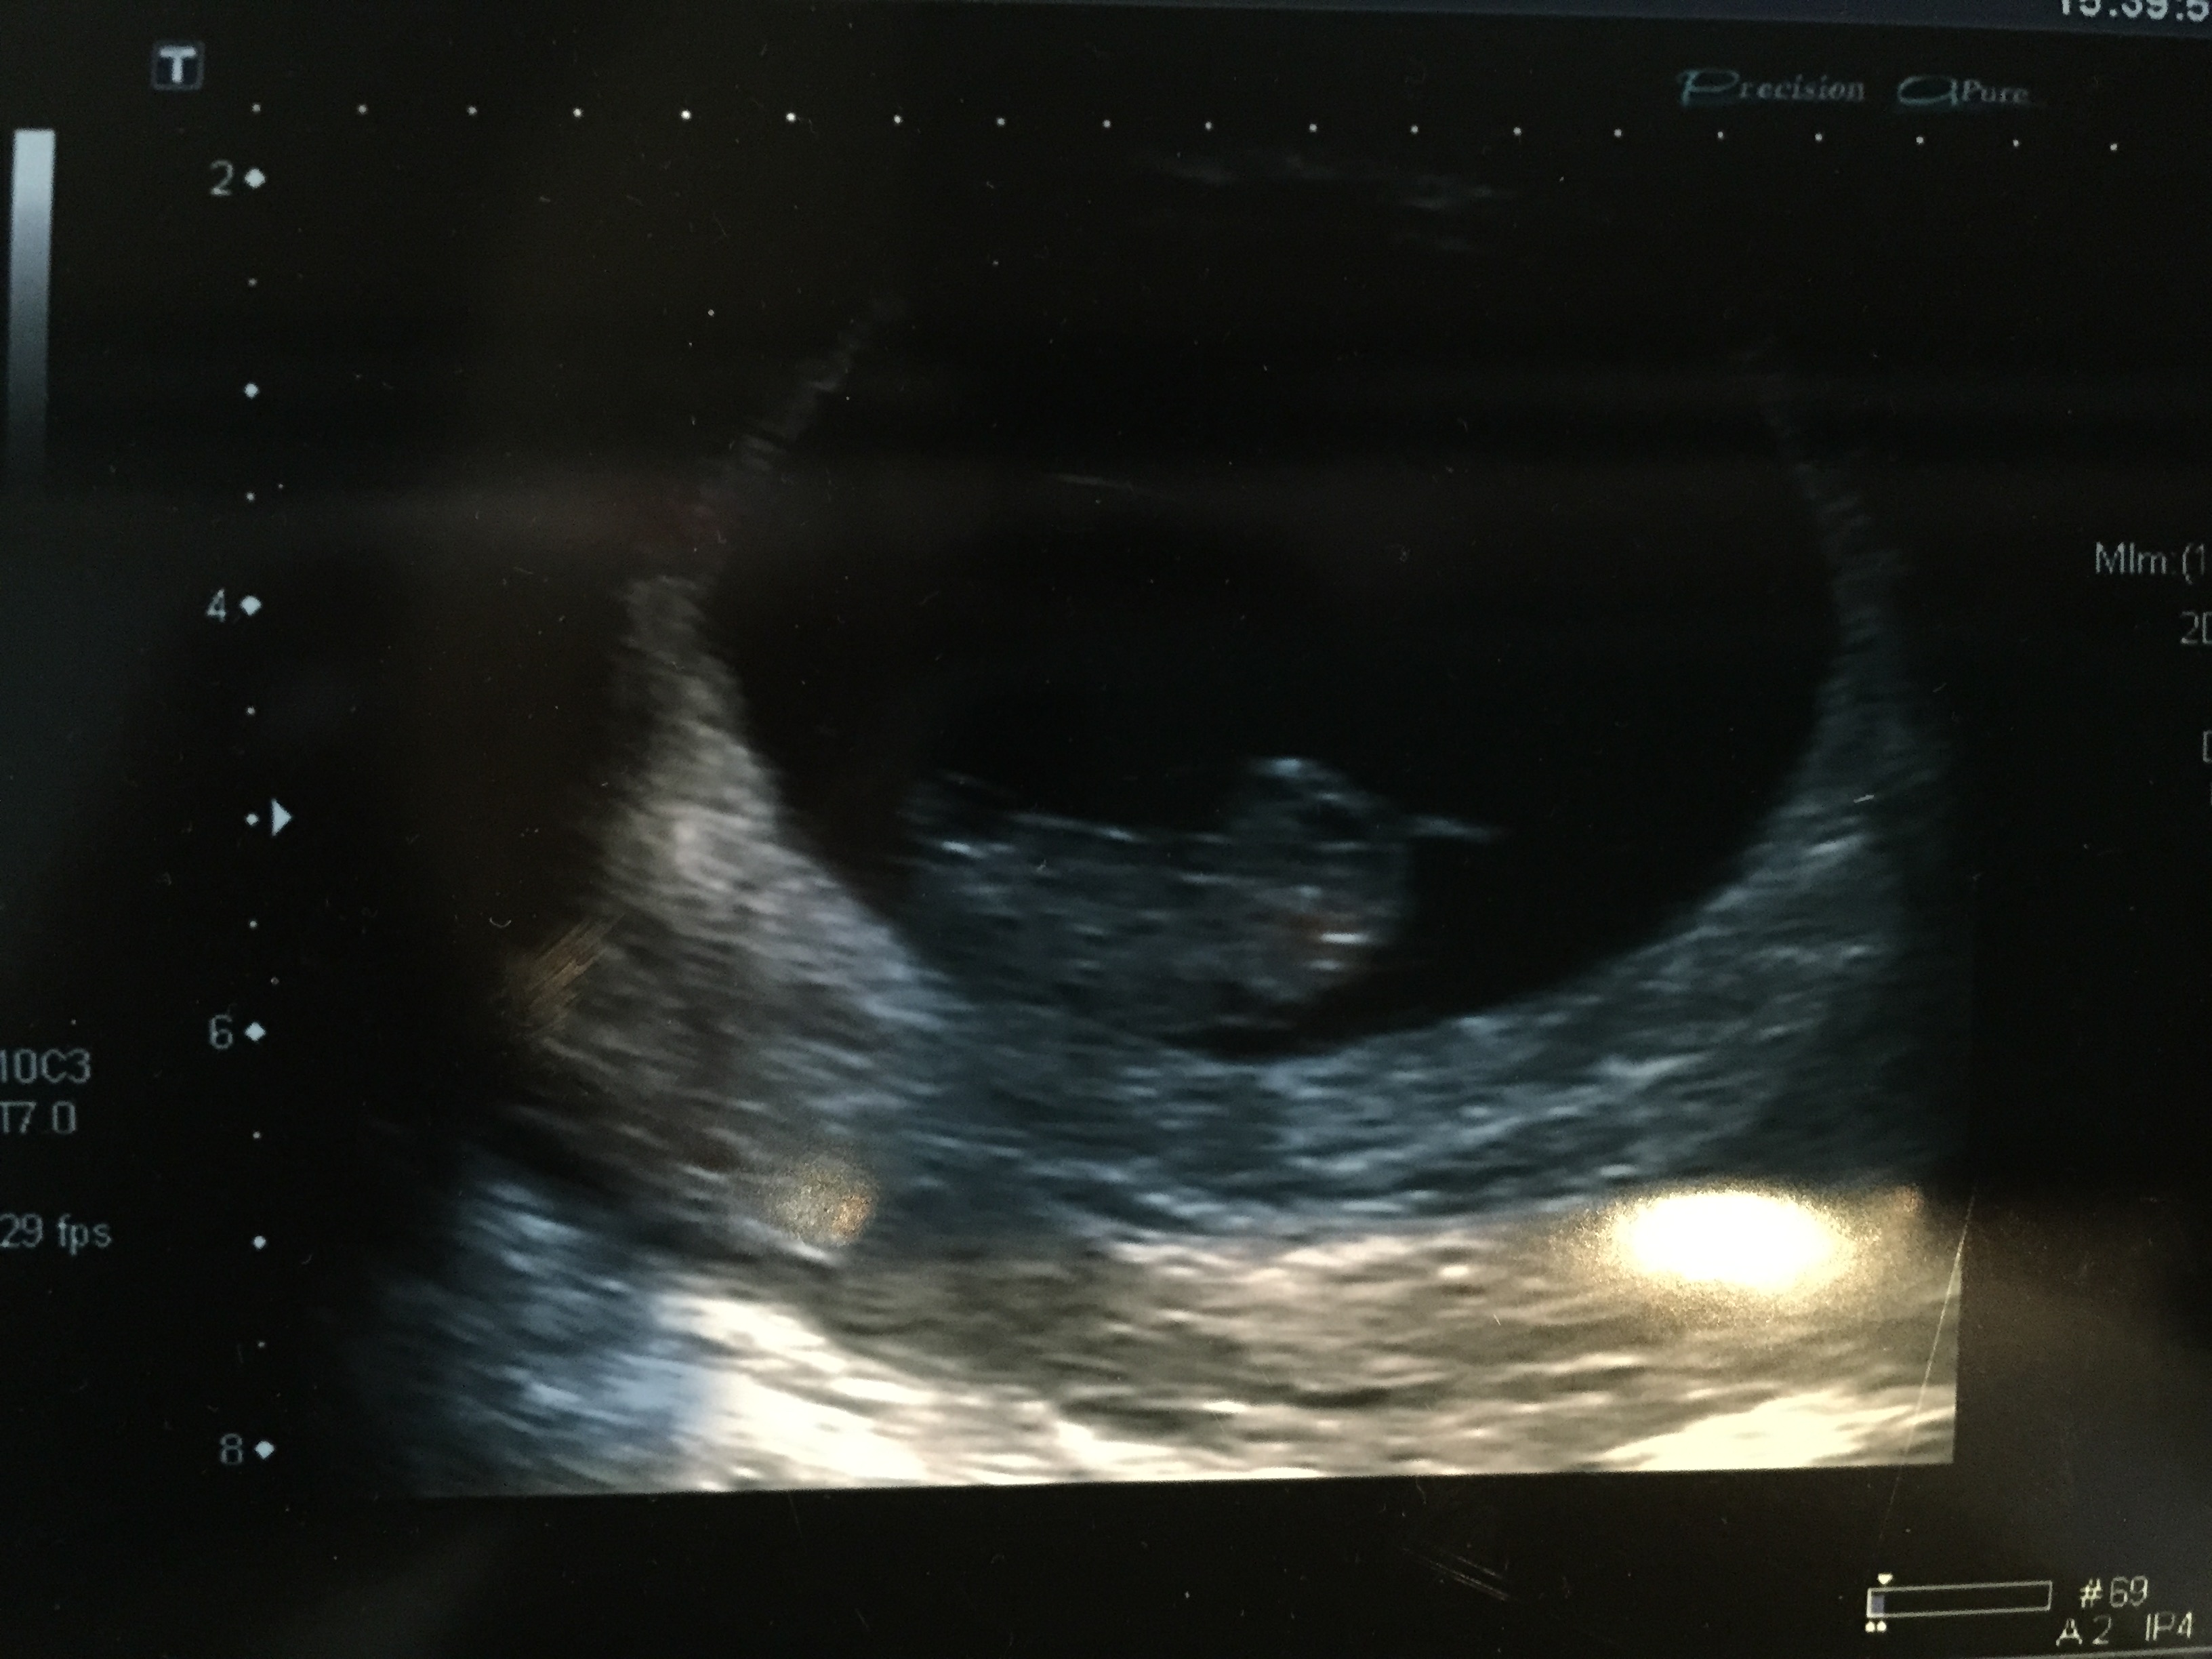

Attachment 22633

Not sure if this picture worked. Could someone tell me what is the placenta? I vaguely remember the tech saying the yolk sac was around babies head, but looks to me that the placenta is the white on the left of the picture. As well, baby measured 9 weeks 2 days, but based on my dates (opk) was 8 weeks 6 days. I know they say Ramzi is only accurate between 6-8 weeks. Why is that and would this still be accurate (or as accurate as Ramzi is)? Oh and ultrasound was abdominal.